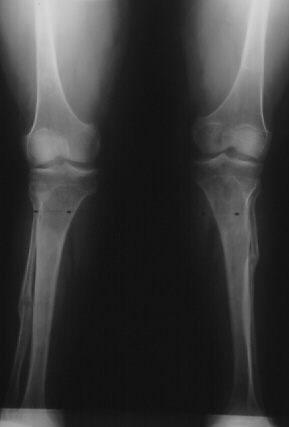

SPONDYLO-EPI-METAPHYSEAL DYSPLASIA WITH JOINT LAXITY (SEMDJL)

Radiographic features: